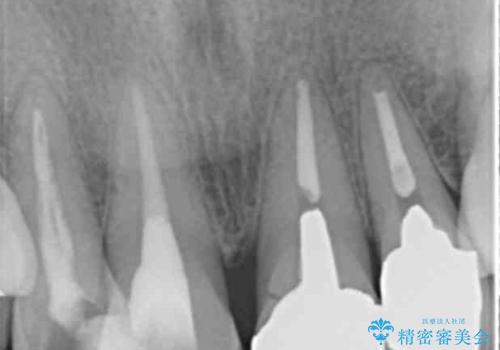

- 前歯のぐらつき、見た目の改善を希望され来院されました。

ぐらつきのある歯は、破折が認められ、その他前歯も不十分な根管治療や不適合なクラウン、レジン修復により審美障害が起きています。

問題を一つづつ丁寧に解決し、前歯の審美性の改善を計画します。